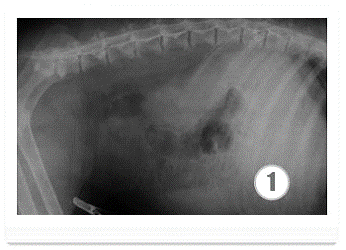

Рентгенография проводится для оценки размеров печени и выявления асцита.

артрофического цирроза. На снимке хорошо различимы увеличенная (рис 1) и уменьшенная

(рис 2) печени животных.